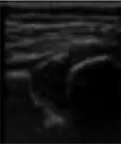

In this study, the weights of each anatomical structure obtained by entropy weight method were respectively bony rim point: 0.29, lower iliac limb point: 0.41, glenoid labrum: 0.30. That means the last weighted score of ultrasound image quality = bony rim point × 0.29 + lower iliac limb point × 0.41 + glenoid labrum × 0.30 (Figure 4). And the proportion of the final weighted score of ultrasound image lower than 3 in each month were 16%, 20%, 14%, 14%, 33%, 27%, 43%.

FIGURE 4

www.frontiersin.org

Figure 4. (A) The image structure of the 5-month-old subject was not clearly displayed, scoring only 2.30. (B) In contrast, the 8-month-old subjects had a clearly displayed image structure, achieving a score of 4.01.